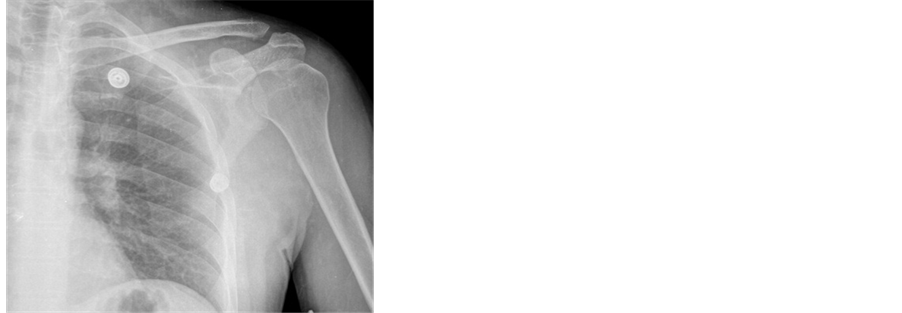

1.1. Case 1

A 34-year-old male presented to our emergency room with left shoulder pain after a motorcycle accident. The pain was localised to the anterior aspect of the shoulder. He demonstrated only 90 degrees of active flexion and abduction with intense pain. A lesion suspected to be a coracoid fracture seen on an anteroposterior roentgenograph (Figure 1). The lesion was completely delineated by computed tomography (Figure 2). The patient was treated with analgesics and a simple arm sling for 3 weeks. During this period, passive shoulder exercises (mostly pendular) were performed. At the 3-week follow-up visit, the patient was symptom-free and active shoulder exercises were started. Follow-up X-rays at 3 months revealed evidence of bony union of the coracoid process. At the 6-month follow-up, he exhibited full range of motion with no symptoms.

Figure 1. Anteroposterior roentgenograph of case 1. Fracture clear image in this roentgenograph is not available.